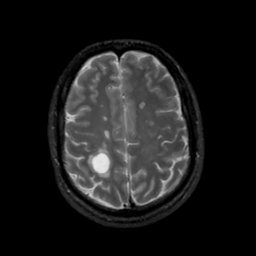

MR Study #6, March 17, 1991 -- Slice #37

[Home][Help][Clinical][Tour 1][Tour 2] Slice 37